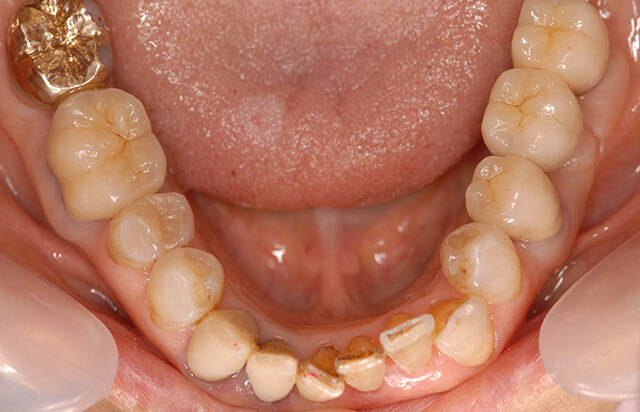

治療前

上顎右側第一小臼歯は、重度の歯周病に罹患し保存が困難な状態でした。上顎第二小臼歯部と下顎右側第一大臼歯部は、部分的に歯槽骨の吸収が進行していたため、残存歯が少ないこともあり再生療法を適応し積極的に保存できるように試みました。全顎的に歯肉が薄く退縮傾向が認められたため、補綴治療(被せ物)を行う部位は、歯周外科により厚みのあるブラッシングしやすい歯肉に改善するように計画しました。大臼歯部は、インプラント治療により咬合回復を行っています。

治療後

左右大臼歯部は、インプラント治療により咬合回復されました。補綴物(被せ物)周囲の歯肉は、歯周外科(遊離歯肉移植術・上皮下結合組織移植術等)を行うことでブラッシングしやすい厚みのある健康な歯肉に改善できています。歯肉退縮を起こしていた上顎前歯部は、厚みのある歯肉に改善されたため歯肉退縮の予防が期待できます。

治療後14年

治療終了後14年経過の状態です。上顎は、14年経過していますが歯周組織は安定し歯肉退縮もほとんど認められません。右下第一大臼歯は、治療後13年目に歯根破折を起こし、現在はインプラントに置き換わっています。抜歯後早期埋入を行うことで、治療期間はおよそ10ヶ月程度で抜歯前の咬合を回復することができました。レントゲン写真からも分かるように、BIOHORIZON‘S製インプラントは周囲の骨が天然歯に近い状態を維持できるため、非常に予後が安定しています。14年前に埋入した3i社製インプラントも、現在まで良好に機能しています。